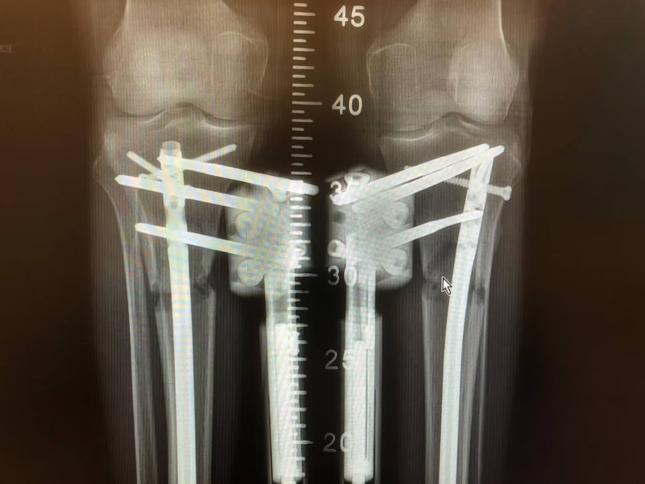

چھوٹے قد والے افراد میں ٹانگوں کی سرجری کروا کے چند انچ قد بڑھانے کا رجحان تیزی سے مقبول ہو رہا ہے۔ تاہم یہ علاج کتنا موثر ہے اور اس کے نقصانات کیا ہیں؟